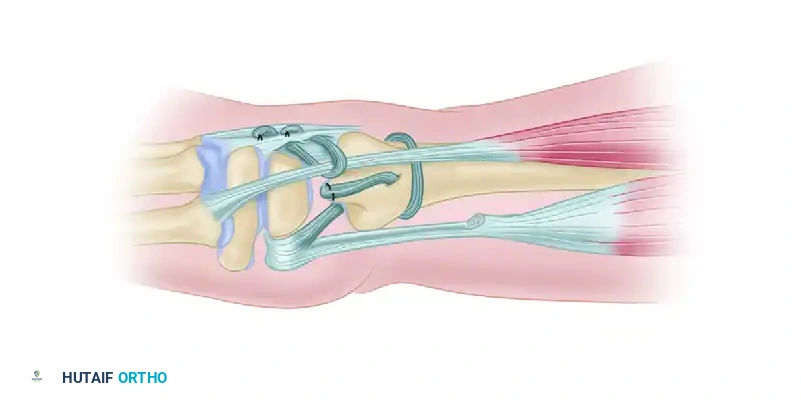

Step 4: Ulnar Tenodesis

* To prevent proximal migration and provide additional longitudinal stability, a tenodesis of the distal end of the ulna is performed using a split portion of the flexor carpi ulnaris (FCU) tendon.

Figure: Tenodesis of the distal end of the ulna using a split portion of the flexor carpi ulnaris tendon.

Figure: Detailed view of the ulnar tenodesis securing the distal ulna.

Step 5: ECU Stabilization

* In chronic instability, the ECU tendon often subluxates volarly during wrist flexion and pronation.

* The ECU is anchored dorsally using a separate tendon loop or extensor retinaculum flap to maintain its position as a dynamic DRUJ stabilizer.

Figure: Final appearance after anchoring the extensor carpi ulnaris tendon dorsally by a separate tendon loop to prevent subluxation.